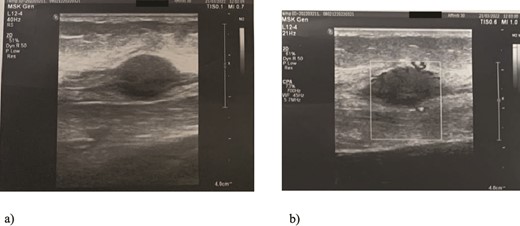

We present a case of a 49-year-old, female patient who presented at our clinic complaining of a growing painful mass with a diameter of ⁓3 cm in her left calf. The patient noticed the mass 2 months before the clinical exam and according to the anamnestic data it was growing progressively, becoming more painful, but only when touched, not spontaneously. She was first seen in another clinic, an ultrasound was performed and excision in local anesthesia was suggested. On presentation, clinical and ultrasound examinations were performed. Clinical exam revealed presence of a soft tissue mass on the medial side between the proximal and medial third of the left calf, of ⁓3 cm. It was placed deep in the subdermal area, mobile and not connected to the fascia. The ultrasound showed a heterogeneous, but predominantly hypoechoic mass with increased through transmission and increased vascularization (Fig. 1). Magnetic resonance imaging (MRI) was performed, confirming the presence of a soft tissue tumor in the subcutaneous tissue of the left calf (Fig. 2). Wide resection of the mass under spinal anesthesia was scheduled. Macroscopy of the specimen showed a whiteish soft fragment measuring 2 × 2 × 0.8 cm, microscopically composed of fibroblastic stroma with myxoid degeneration and immature osteoid embedded in between atypical osteoblasts with inconspicuous mitotic activity (Fig. 3). Foci of chondroid matrix with atypical chondrocytes were present. Necrotic and calcified bony trabeculae with osteoblastic rimming and adipose tissue with skeletal muscle were present on the periphery. The proliferative index, Ki67 was ⁓5%, thereupon a diagnosis of low-grade ESOS was made (Fig. 4). The regular staging follow-up was performed with chest and abdominal computed tomography (CT). No signs of metastatic disease were detected. The bone scan with Tc99m showed an increased uptake on the left iliac bone, highly suspected of Paget disease. Another surgery was scheduled. This time, re-resection procedure to achieve negative margins, as well as a biopsy of the iliac wing was performed. Negative margins were accomplished with the re-resection procedure. Grossly, the iliac bone biopsy was composed of five bony fragments measuring 0.5–1.5 cm. Microscopy showed sclerotic and irregularly shaped anastomosing, lamellar bony trabeculae with focal irregular calcification. The trabeculae contain osteocytes without atypia, rimmed with reactive osteoblasts, as well as multinucleated osteoclast giant cells. Granulation tissue with focal collagen deposition was present focally in between the bone trabeculae. Focal bone marrow was present. The microscopic analysis was consistent with the late (sclerotic) phase of Paget disease of bone (Fig. 5). On the last follow-up exam, 2 years after the surgery there is no evidence of local recurrence.

MRI findings of the tumor (arrows): (a) T1 image, coronal view; (b) T2 image, sagittal view; (c) T1 image, axial view revealing presence of a well-defined soft tissue tumor positioned in the subcutaneous fat tissue of the left calf with size of 3 cm and swelling of the surrounding muscles.